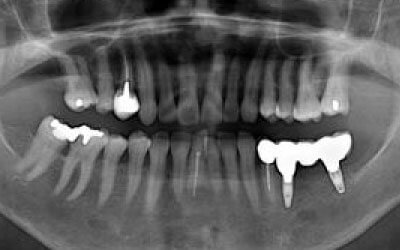

CTでは骨や歯の状態などを3次元で見ることができ、正確な距離を測ることも可能です。

骨の厚みや傾き、神経の位置などを事前にしっかり計測することで安全なインプラントが可能となります。

骨が薄い場合は、そのままインプラントすることはお勧めできません。

ただ、事前に骨を増やす治療をしたり、インプラントと同時に骨を増やす治療をしたりすればインプラントをすることは可能です。